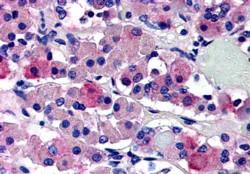

APR12076G (5 μg/ml) staining of paraffin embedded Human Anterior Pituitary Gland. Steamed antigen retrieval with citrate buffer pH 6, AP-staining.